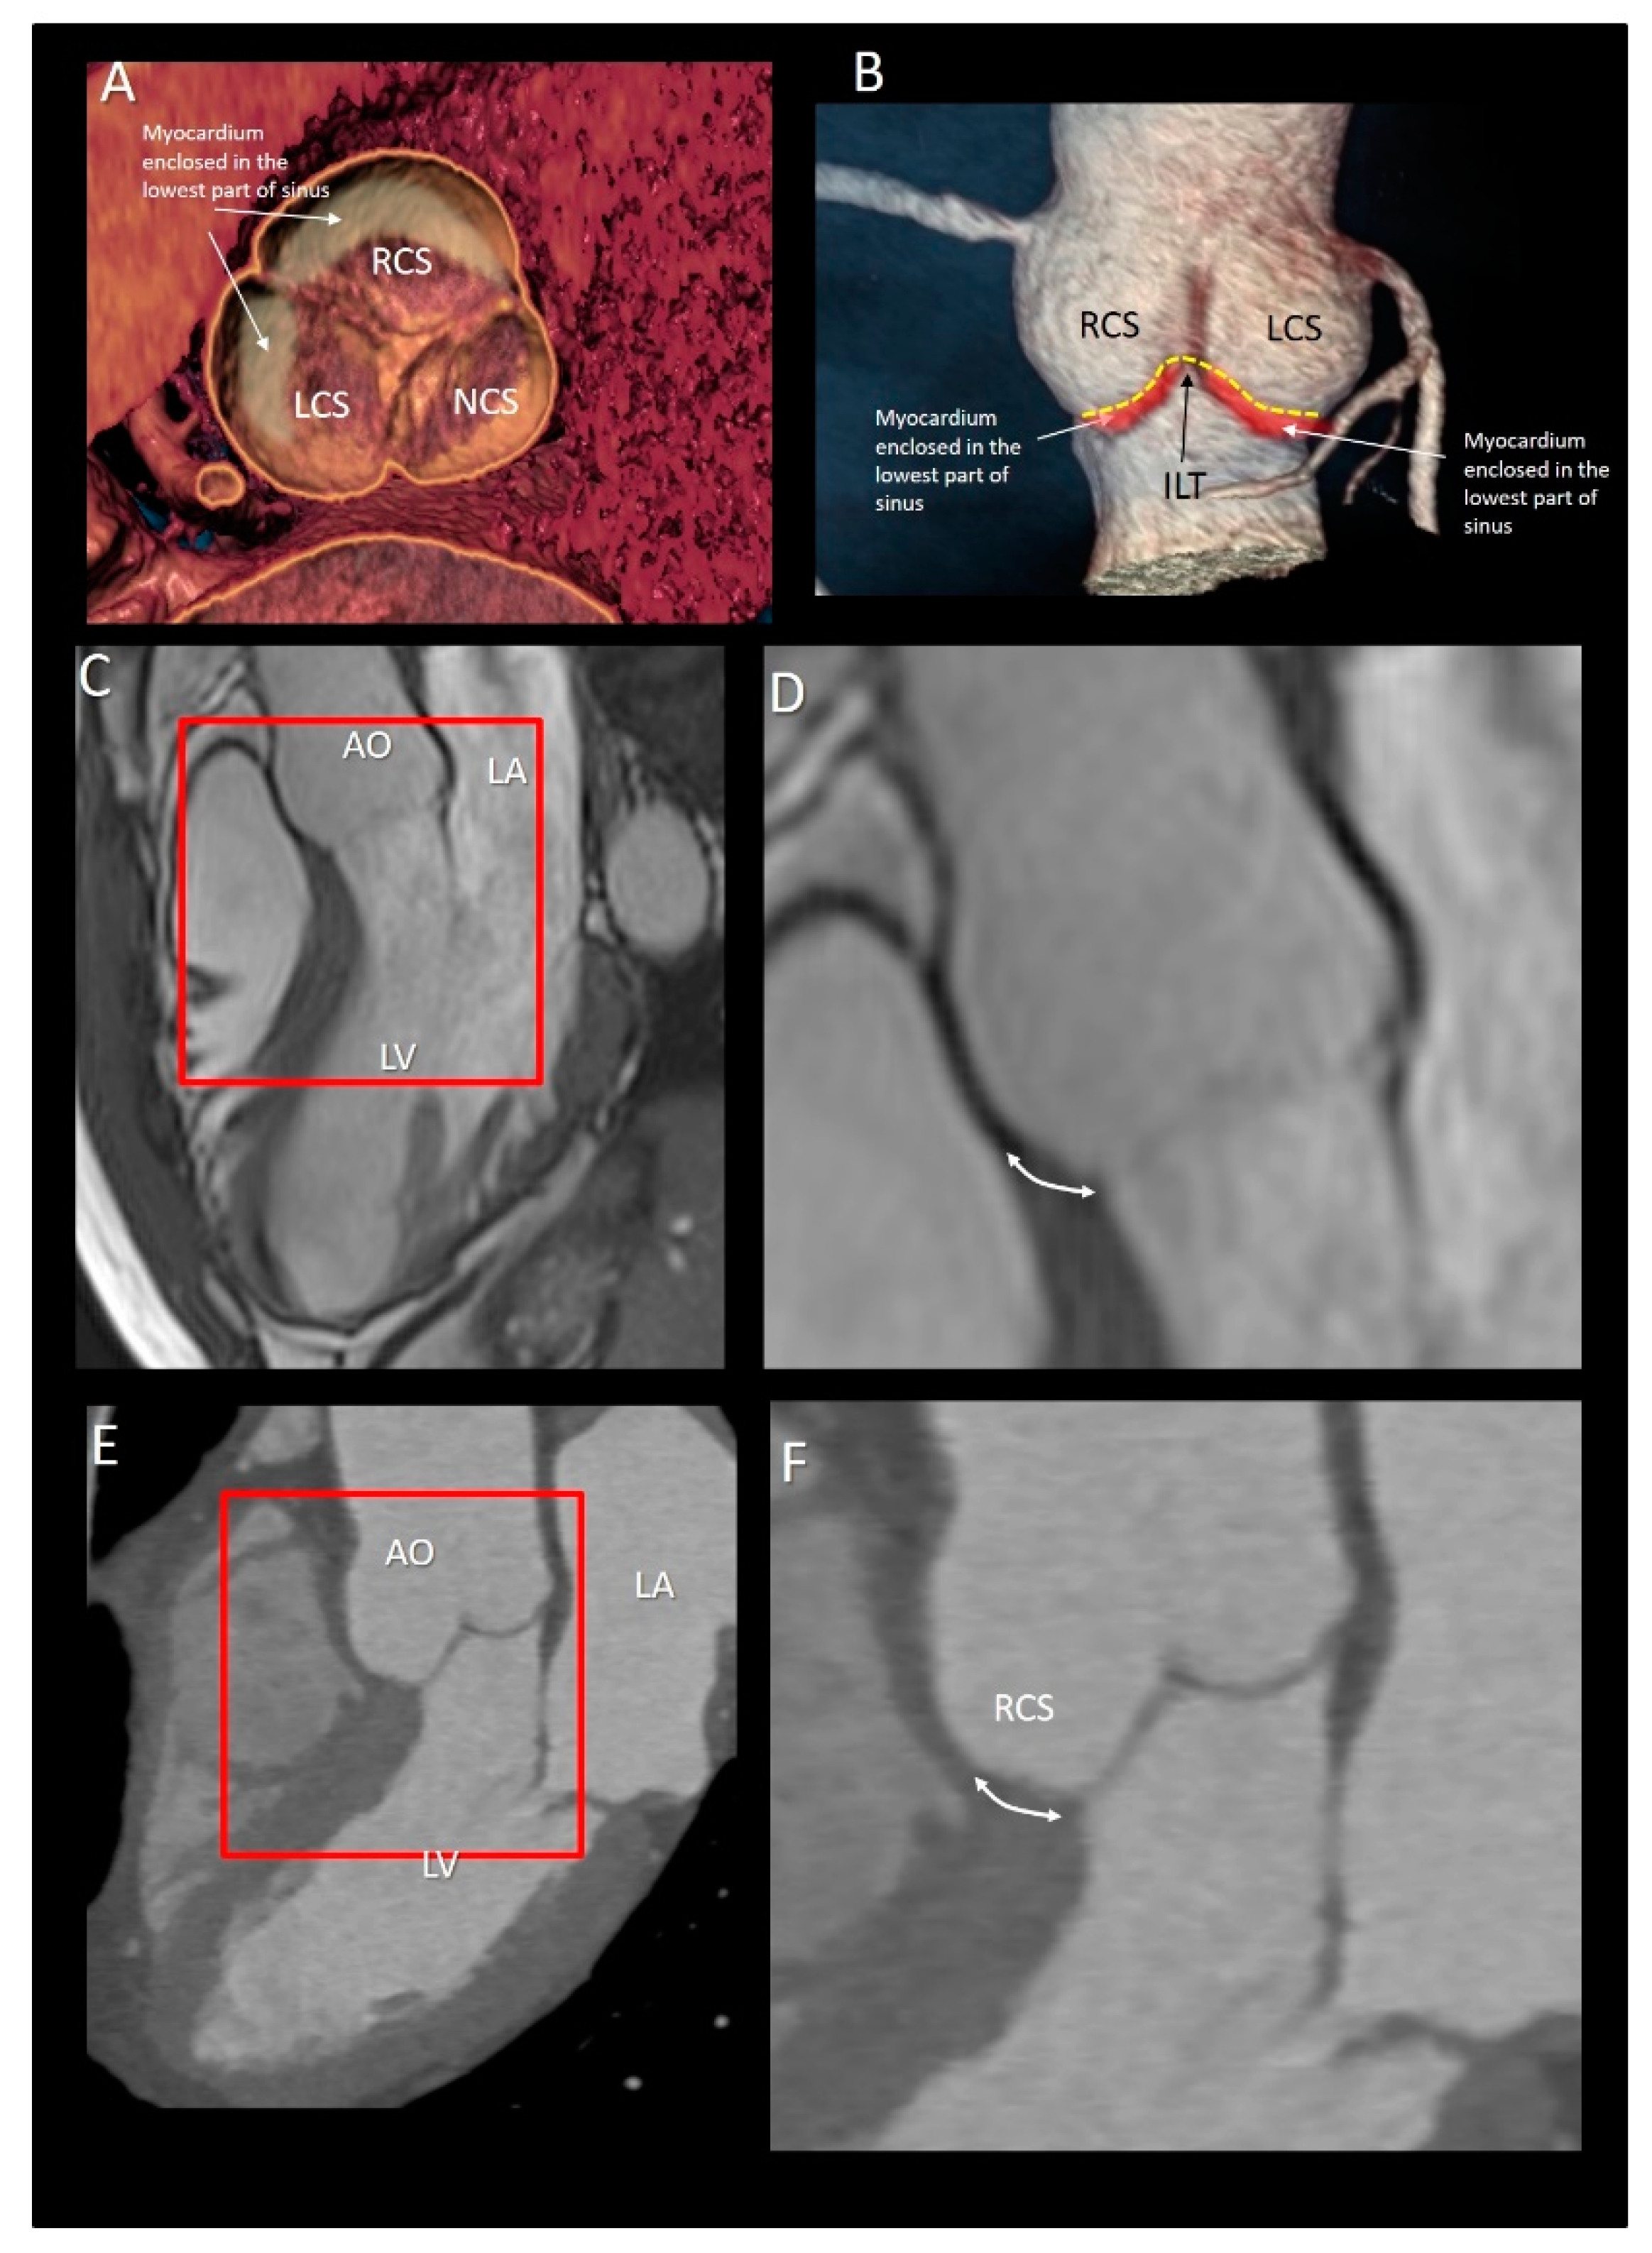

3.3.2. The Muscular Component of VAJ

3.4. The Fibrous Component of VAJ